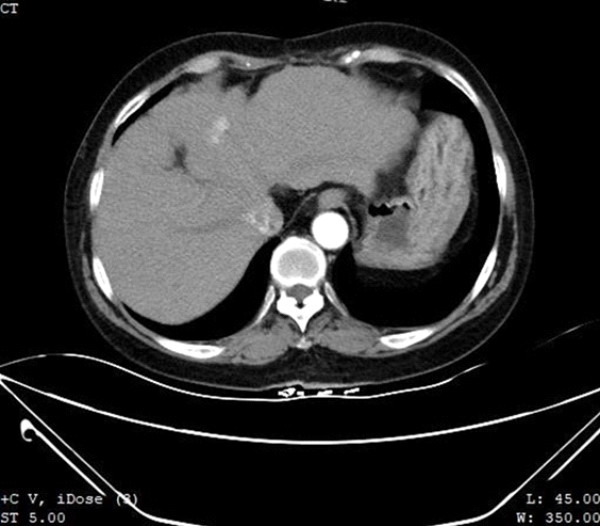

64세 여성으로 30년 전부터 만성B형 간염 보균자였으며, 우측간엽 S7부위 간암으로 분절간 절제술과 비장절제술을 받았습니다. 3개월 전에 MR로 S4 분절에 생긴 재발성 간암 의중으로 본원으로 전환된 환자였습니다. 본원에서 Contrast-enhanced CT(조영제 증강 CT검사)를 실시하여 좌엽 S4 분절에 1.5센티미터 크기 저음영의 불규칙한 종괴가 발견되었습니다. 동맥기 문맥가 정맥기 모두에서 재발성 간암에 합당한 소견을 보였습니다.

형태 1. Contrast-enhanced CT 소견으로 좌엽 S4 구역에서 1.5센티미터 크기의 저밀도 음영이 발견되었으며, 조영제 투여 후 동맥기에서 균일하지 않은 증강을 보여주었습니다.